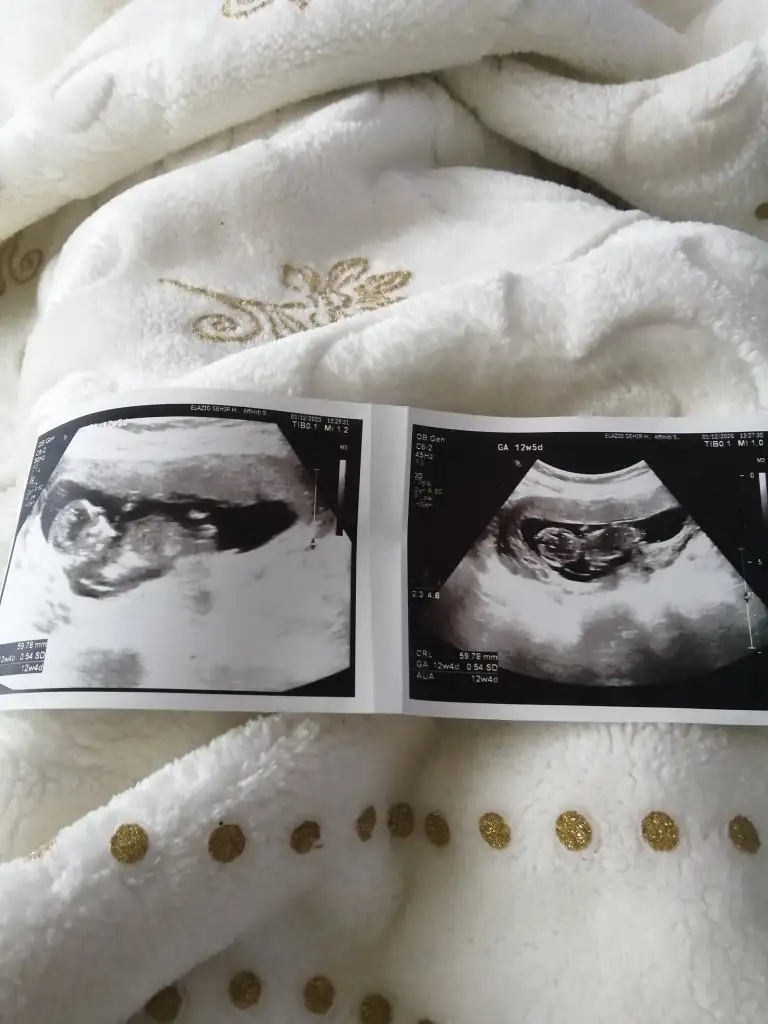

Evet nuba göreTeşekkür ederimramziye göre erkek siz bu fotoğrafta nuba göre mi tahminde bulundunuz acaba

Erkek görünüyor emin olamadimMerhaba benimki de 12 haftalık sizce cinsiyet nedir kendini sakladı ilk bebeğim sağlıklı hayırlı olsun da insan merak ediyor işte![]()

En iyi 11 12 13 haftalar olmalı şimdilik sanki erkek yinede istediğim haftalar olursa paylasin10.hafta acaba belli olan bişi var mı☺

En iyi 11 12 13 haftalar olmalı şimdilik sanki erkek yinede istediğim haftalar olursa paylasin